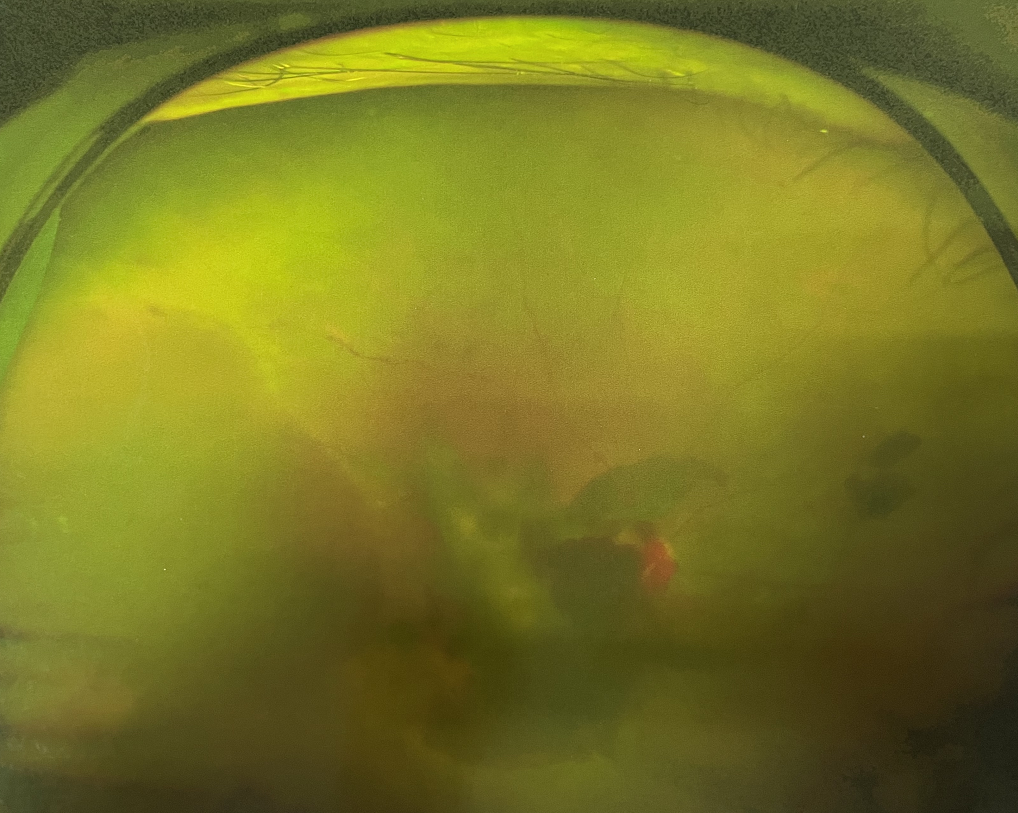

眼底出血多指玻璃體內(nèi),眼睛更深處的視網(wǎng)膜出血。通常情況下,肉眼難以發(fā)現(xiàn)眼底出血,而且發(fā)病初期眼睛也無明顯癥狀,只有借助專業(yè)的眼底檢查儀器才能觀察到異樣。那么眼底出血嚴(yán)重嗎?

眼底出血嚴(yán)重嗎?對于已出現(xiàn)黃斑水腫、視網(wǎng)膜新生血管的患者,根據(jù)眼底血管造影、oct等檢查結(jié)果,給予玻璃體腔注射抗VEGF藥物及激光治療,可以減輕黃斑水腫,使視網(wǎng)膜新生血管消退,以免進一步發(fā)生玻璃體出血、視網(wǎng)膜脫離等嚴(yán)重并發(fā)癥的出現(xiàn)。對于玻璃體出血者,傳統(tǒng)認為玻璃體出血3-6個月不吸收再進行手術(shù)干預(yù),但近年來因為顯微手術(shù)設(shè)備及玻璃體切割技術(shù)已非常成熟,故對于1個月不吸收的玻璃體出血者就可以考慮手術(shù),即手術(shù)時機應(yīng)該具體情況具體分析,因人而異。